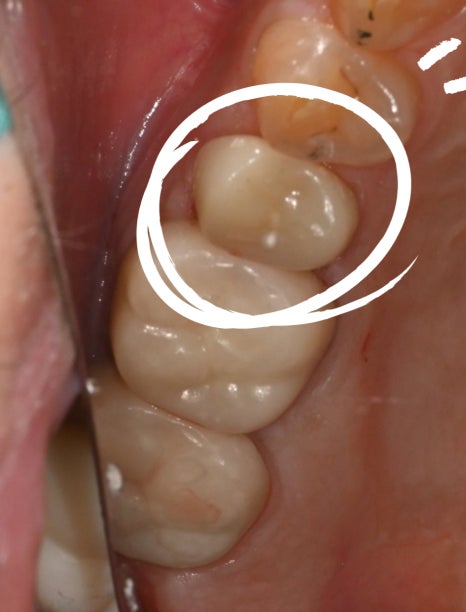

초진내원당시

오른쪽 이가 깨졌는데 시리고 아파요

엑스레이를 확인해보니 충치가 너무 심해 치아가

깨진 상태로 오셨어요.

이렇게 어금니까 깨졌을 때에는

신경치료가 꼭 필요합니다.

<치료 전 / 치료 후>